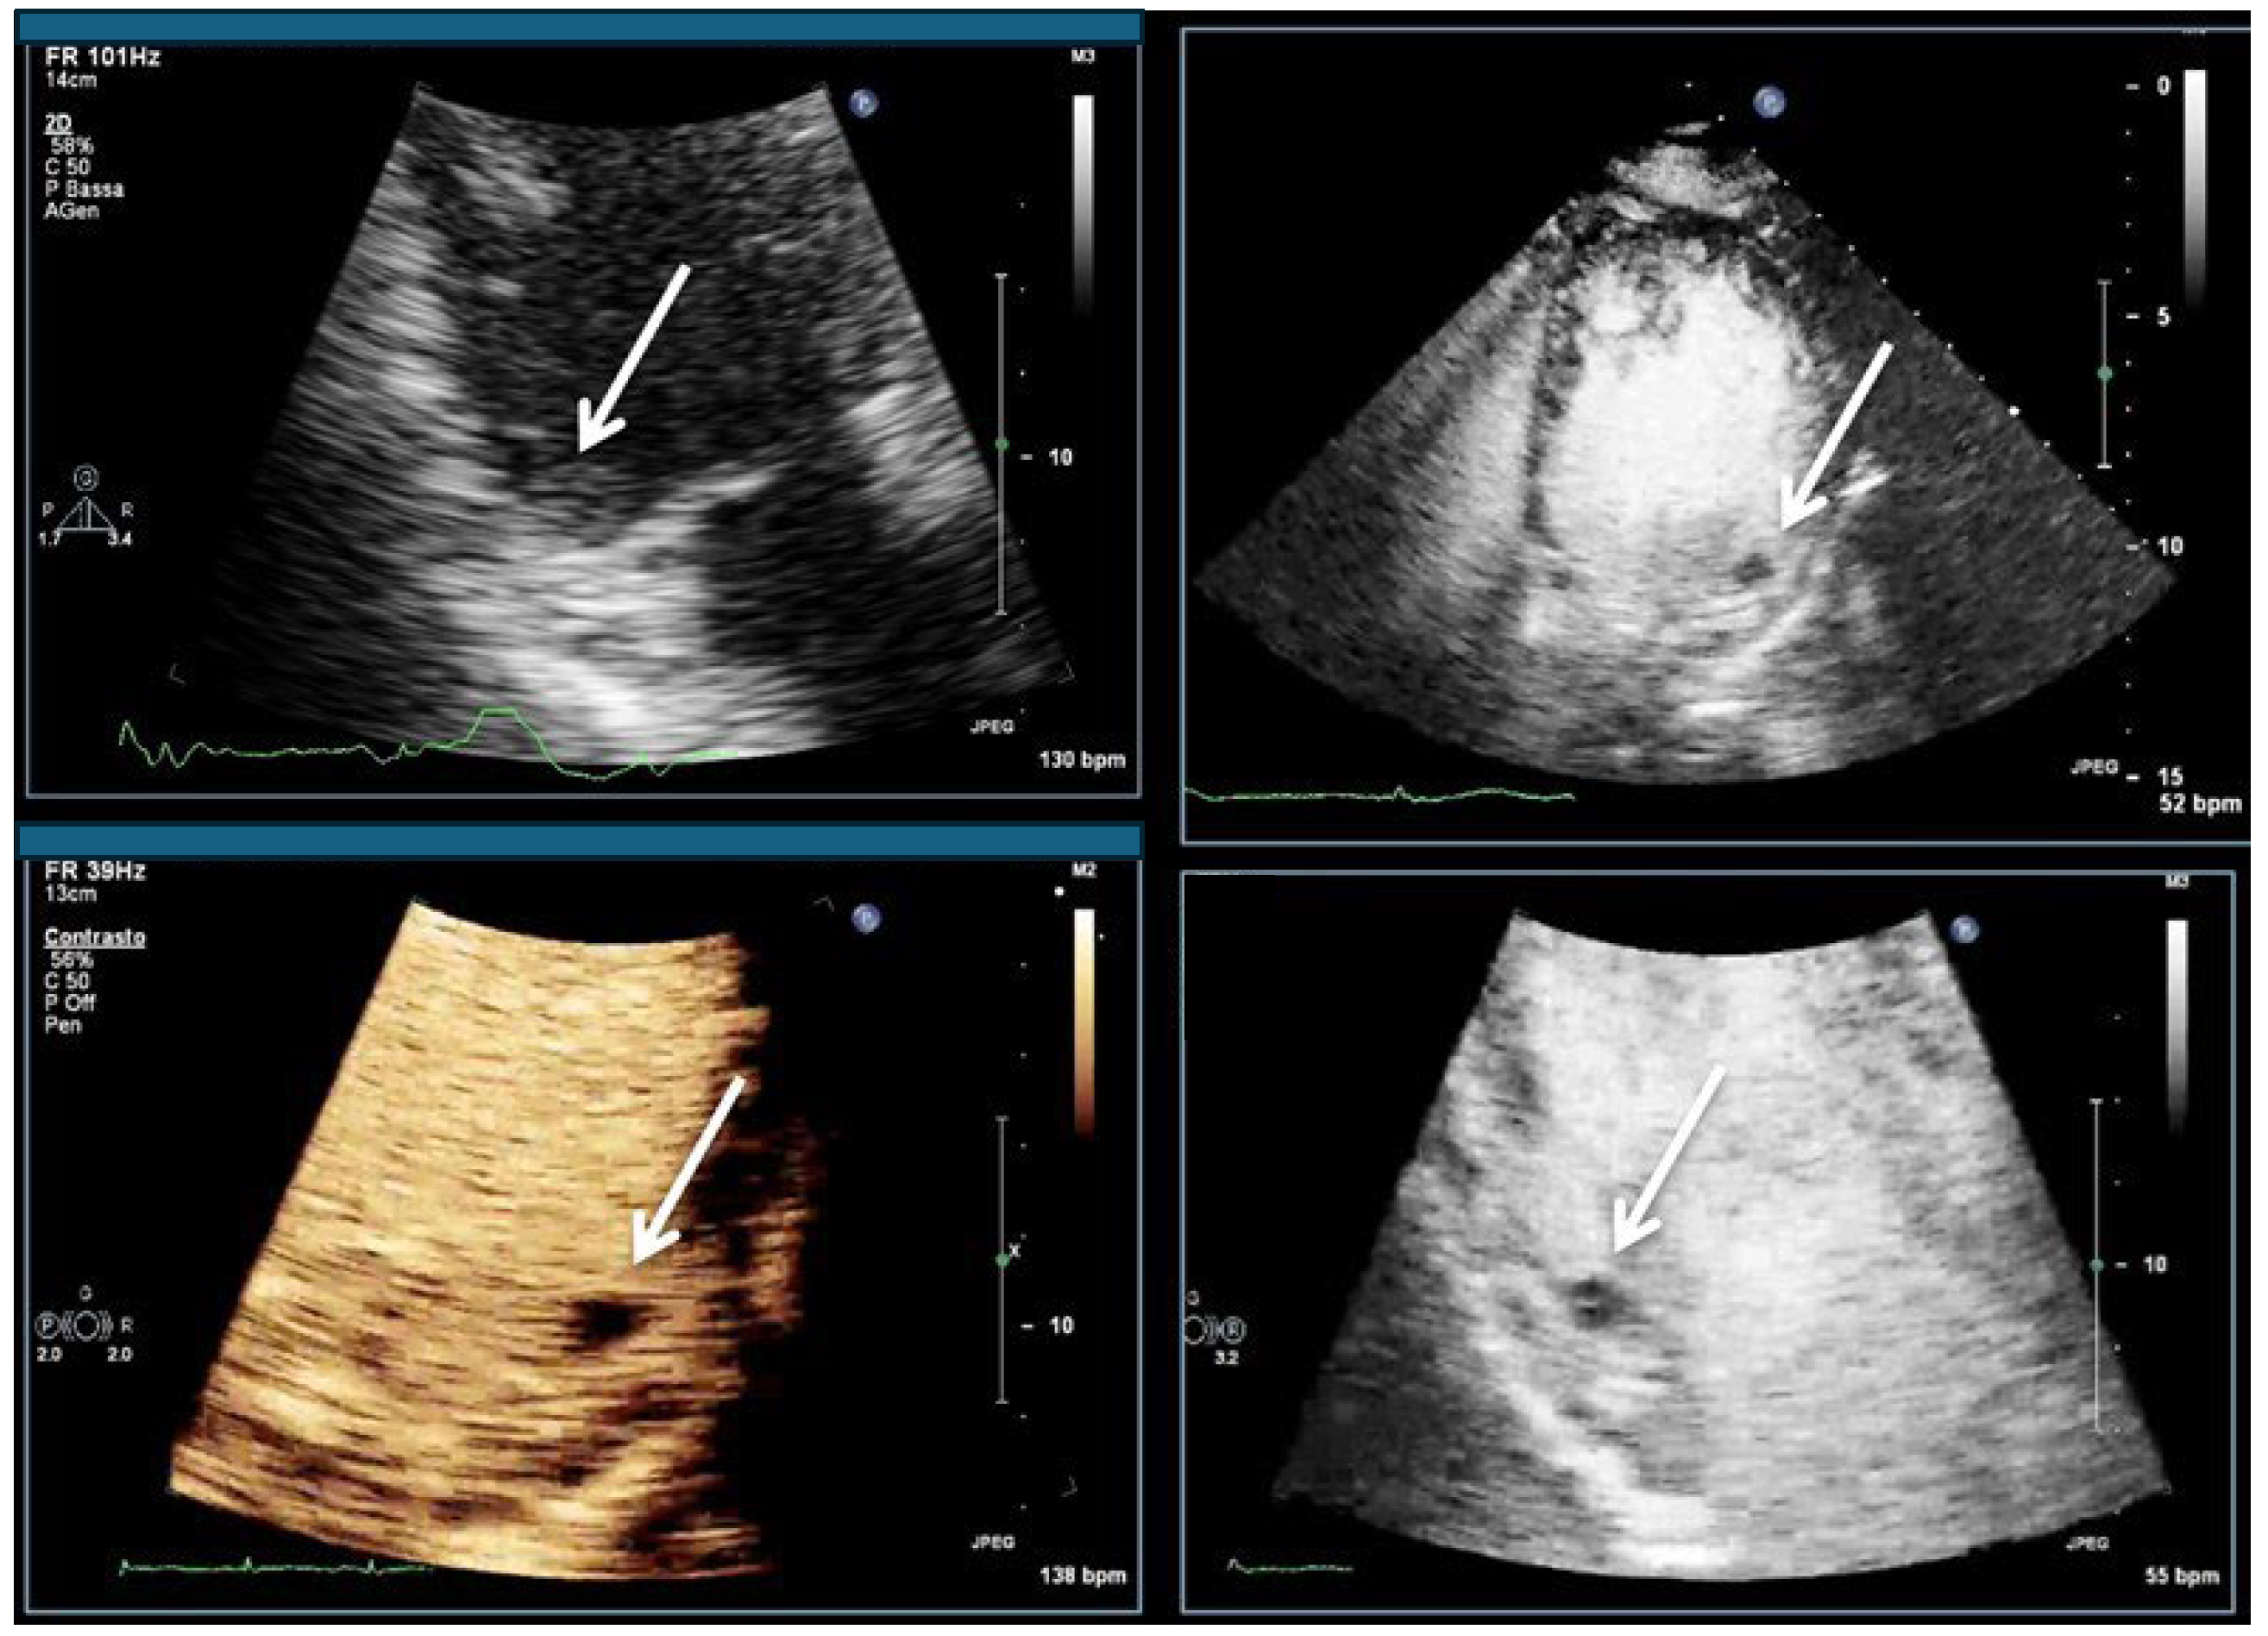

| Imaging method | Low-MI-contrast-specific imaging and intermediate-MI-contrast-specific imaging |

| Imaging planes | standard apical views additional zoomed views sweeps through the region of the suspected thrombus |

| Sector depth/width | Entire LV + 1/3 LA to assess global/regional LV function, zoomed views of the region with the suspected thrombus |

| Focus | At the depth of the suspected thrombus |

| Gain | Adjust to avoid obscuring the thrombus by intensive opacification of the cavity |

| Contrast application | bolus injections |

| Typical findings | 1. echofree mass 2. present in two different imaging planes 3. lump or laminar shape different from trabeculations’ documented size (two orthogonal diameters in at least one of the views), location, type (laminar vs. lump, single vs. multiple), surface (smooth vs. irregular) and mobility |

| DD tumor vs. thrombus | Opacified (vascularized) masses are suggestive of tumors; the vascularization can be demonstrated with myocardial perfusion imaging. CAVEAT: There are malignant tumors which appear avascular on CEUS. Tumors often are attached to normal myocardium. |